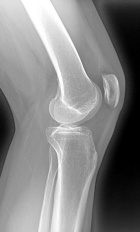

26 year old female with pain and swelling in the right knee for two years

Zoom image: Radiological image Radiological image.